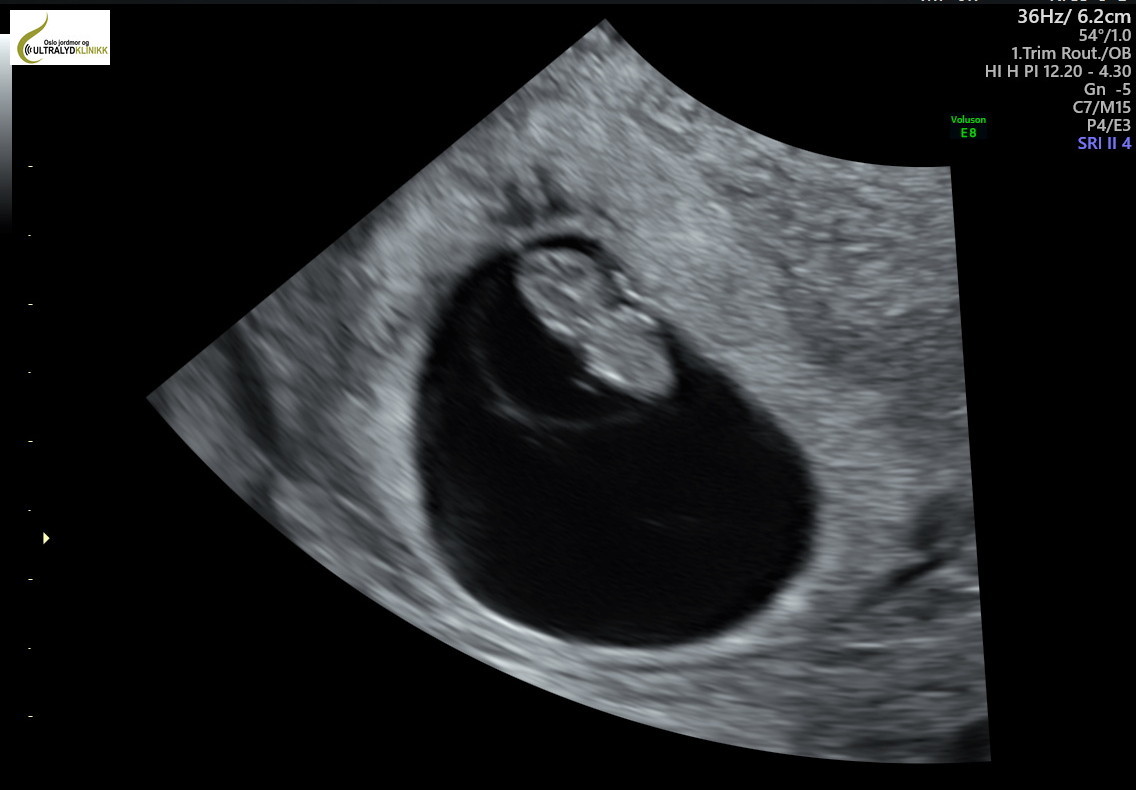

From www.jordmorklinikken.no

Early ultrasound week 6 7 How Early Can An Ultrasound Detect Multiples How early can you see twins on an ultrasound? But the greater the number of. The earliest you can typically expect to see twin fetuses on an ultrasound is around six weeks. An ultrasound between six and 10 weeks will confirm if you’re having multiples. An ultrasound will usually be able to detect a twin pregnancy early on, but. Typically,. How Early Can An Ultrasound Detect Multiples.